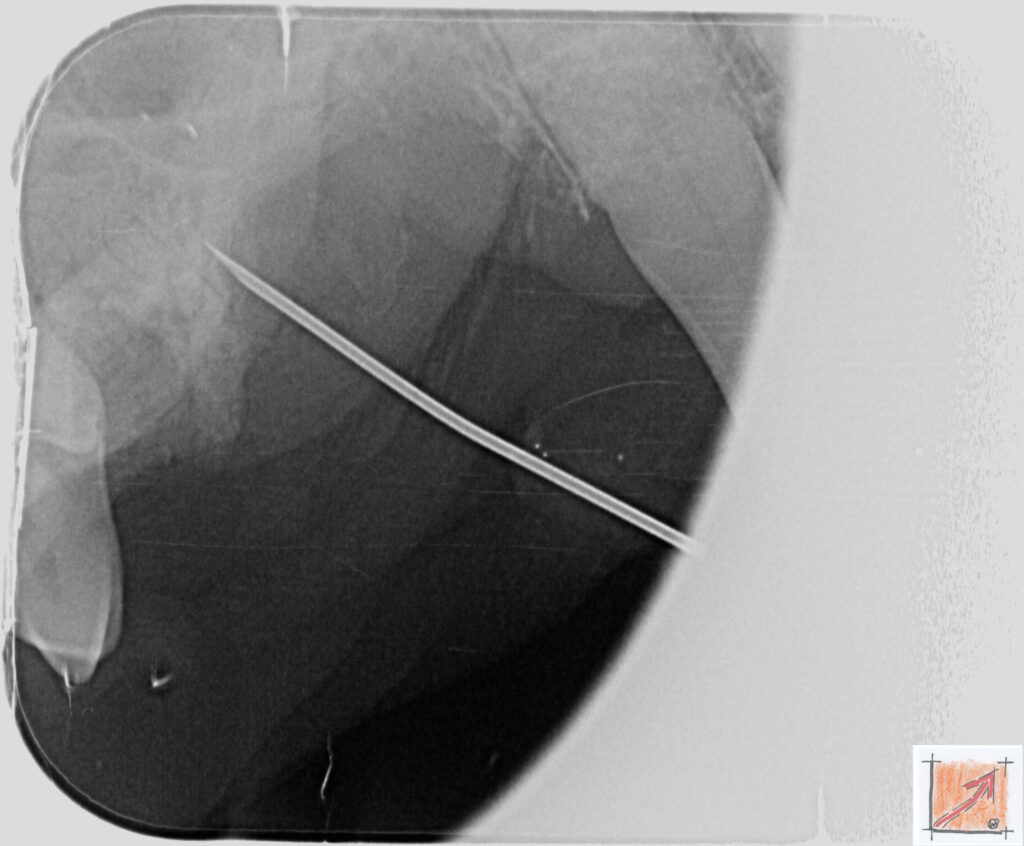

Röntgenbilder vom Thierrischen Orakel bei der Zahn-OP:

Warum Dentalröntgen beim Chihuahua lebenswichtig ist:

Ein Blick hinter die Kulissen von Chihuahua-Zähnen:

In dieser Galerie zeigen wir exklusive intraorale Röntgenaufnahmen einer Zahn-Operation beim Thierrischen Orakel als Chihuahua vom BauFachForum. Während oberflächlicher Zahnstein oft sichtbar ist, verbirgt sich die wahre Gefahr für das Herz meist unter dem Zahnfleischsaum.

Das digitale Dentalröntgen ist der Goldstandard in der modernen Tiermedizin, um parodontale Entzündungsherde und Wurzelabszesse sicher zu diagnostizieren. Für Chihuahuas wie dem Thierrischen Orakel, mit Mitralklappeninsuffizienz ist dieser diagnostische Schritt essenziell. Nur wenn versteckte Bakterienherde an der Zahnwurzel oder mit dem Fachbegriff Apikalabszesse erkannt und saniert werden, kann das Risiko einer bakteriellen Endokarditis oder einfach ausgedrückt einer Herzinnenhautentzündung minimiert werden.

Unsere Aufnahmen von Patienten dem Thierrischen Orakel verdeutlichen den Unterschied zwischen einer rein optischen Zahnreinigung und einer medizinisch fundierten Sanierung unter Röntgenkontrolle.

Chihuahua Mitralklappeninsuffizienz Trachealkollaps:

Wichtig ist im Vorfeld die Zahnhygiene des Chihuahuas. Die Bilder zeigen Dentale Röntgenbilder vom Thierrischen Orakel als Chihuahua-Hund während seiner Zahn-OP. Darstellung von Kieferknochen und Zahnwurzeln zur Diagnose von Parodontitis.

Zahnröntgenaufnahme bei Chihuahua Thierry:

Untersuchung der Zahnwurzeln auf Entzündungsherde als Prophylaxe gegen bakterielle Endokarditis.

Intraorales Dentalröntgen eines Chihuahuas:

Die Bilder zeigen Zähne und Wurzelstrukturen im Unterkiefer zur Planung einer Extraktion bei hochgradigem Zahnstein.